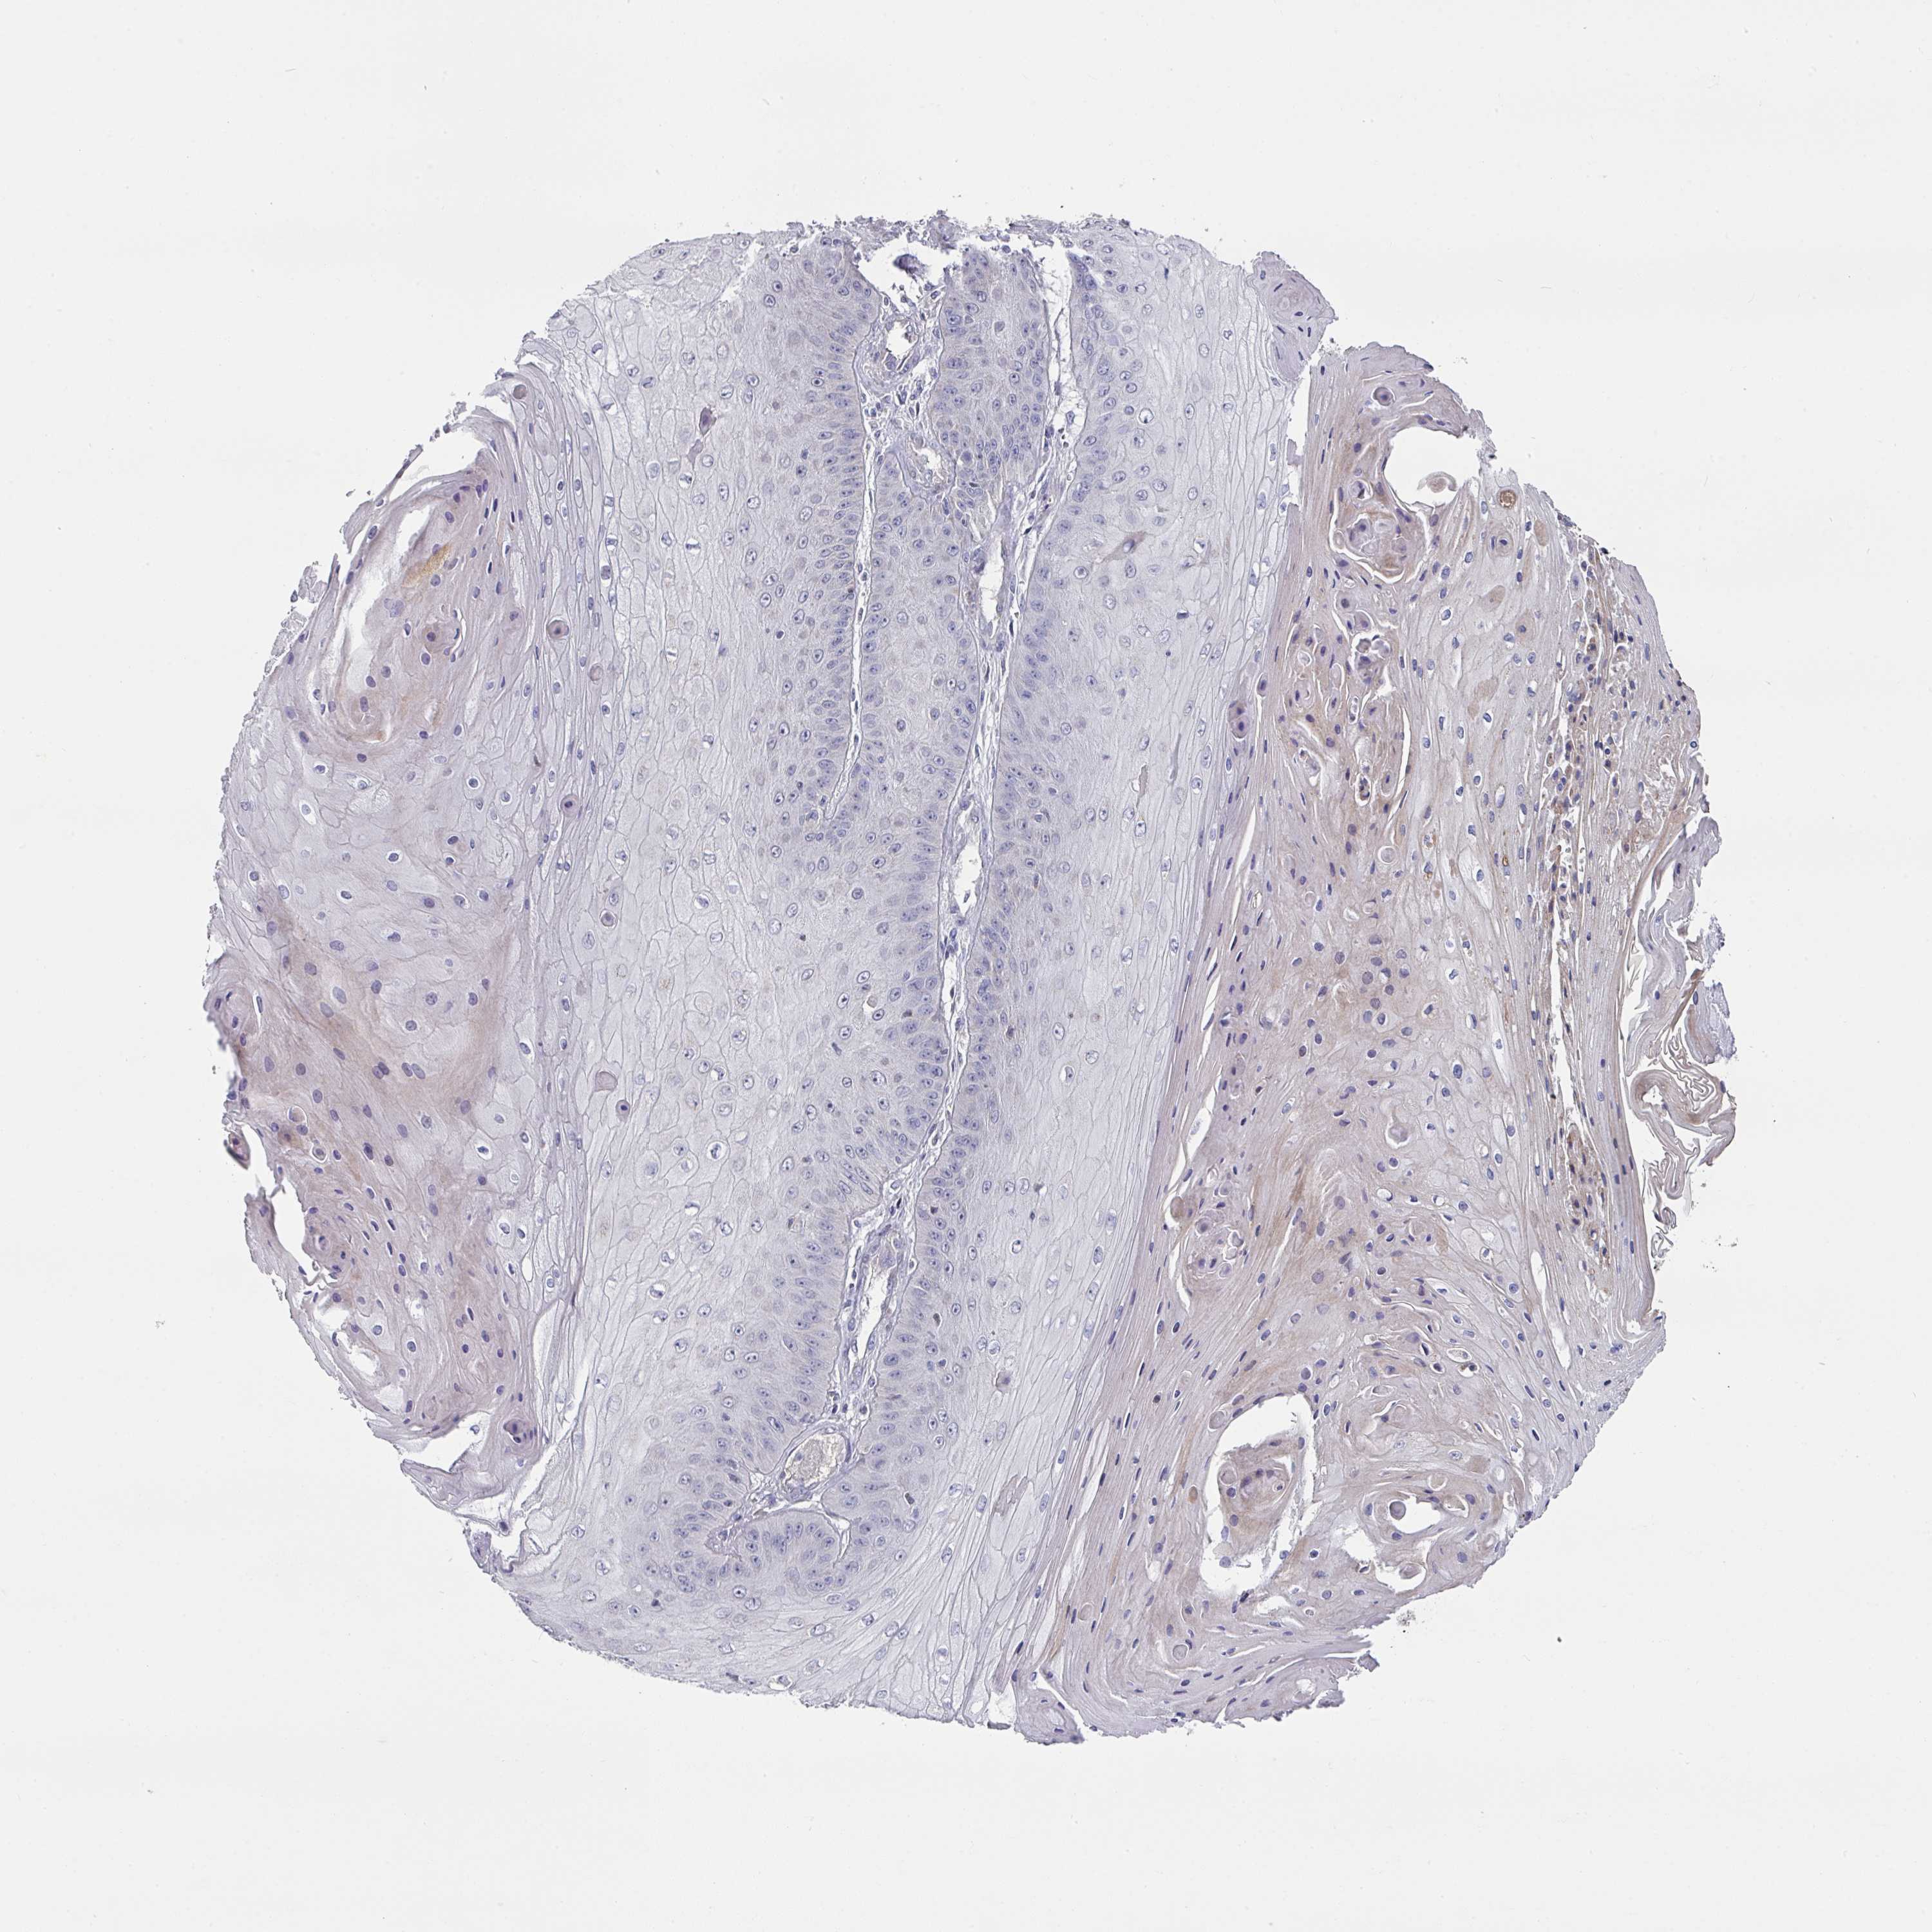

SKIN CANCER - Protein expressioni

A mouse-over function shows sample information and annotation data. Click on an image to view it in a full screen mode. Samples can be filtered based on level of antibody staining by selecting one or several of the following categories: high, medium, low and not detected. The assay and annotation is described here.

Each image is clickable and will lead to virtual microscopy that enables deeper exploration of all samples and also displays staining intensity scores, fraction scores and subcellular localization as well as patient and tissue information for each sample.

Antibody HPA048677

Basal cell carcinoma